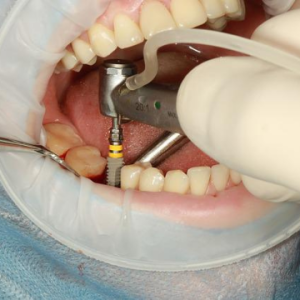

Antecedentes y objetivoLa implantología dental ha revolucionado la rehabilitación bucal, ofreciendo una solución sofisticada para restaurar los dientes perdidos. A pesar de los avances, persisten...

FondoHoy en día los implantes dentales representan una terapia eficaz en caso de edentulismo parcial o total, con una excelente tasa de éxito. A pesar de los resultados obtenidos, durante la...

La estabilidad del hueso marginal y del tejido blando alrededor de los implantes dentales se ha establecido como la principal característica para asegurar la salud del implante.La condición...

Los implantes utilizados para reemplazar los dientes molares presentan problemas de distribución del espacio y contornos de la corona que son exclusivos de estos sitios. Debido a que el diámetro...